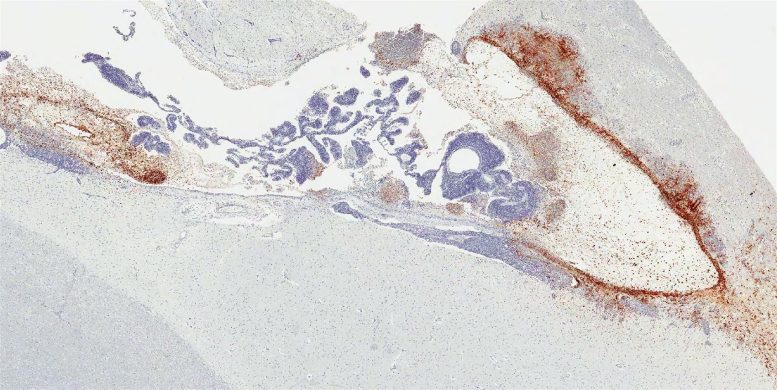

“我们的研究是第一个揭示脑部埃博拉病毒持续存在的藏身之处,以及在非人灵长类动物模型中引起随后致命的埃博拉病毒相关疾病的病理情况的研究,”Kevin解释说。“我们发现,在用单克隆抗体疗法治疗后幸存下来的致命埃博拉病毒暴露的猴子中,约有20%的猴子仍有持续的埃博拉病毒感染--特别是在脑室系统中,脑脊液在其中产生、循环和容纳--即使埃博拉病毒已从所有其他器官中清除。”

Kevin特别指出,两只在用抗体疗法治疗后最初从埃博拉病毒相关疾病中康复的猴子,出现了埃博拉病毒感染的严重临床症状复发并死于该疾病。脑室系统出现了严重的炎症和大量埃博拉病毒感染;其他器官没有发现明显的病理变化和病毒感染。